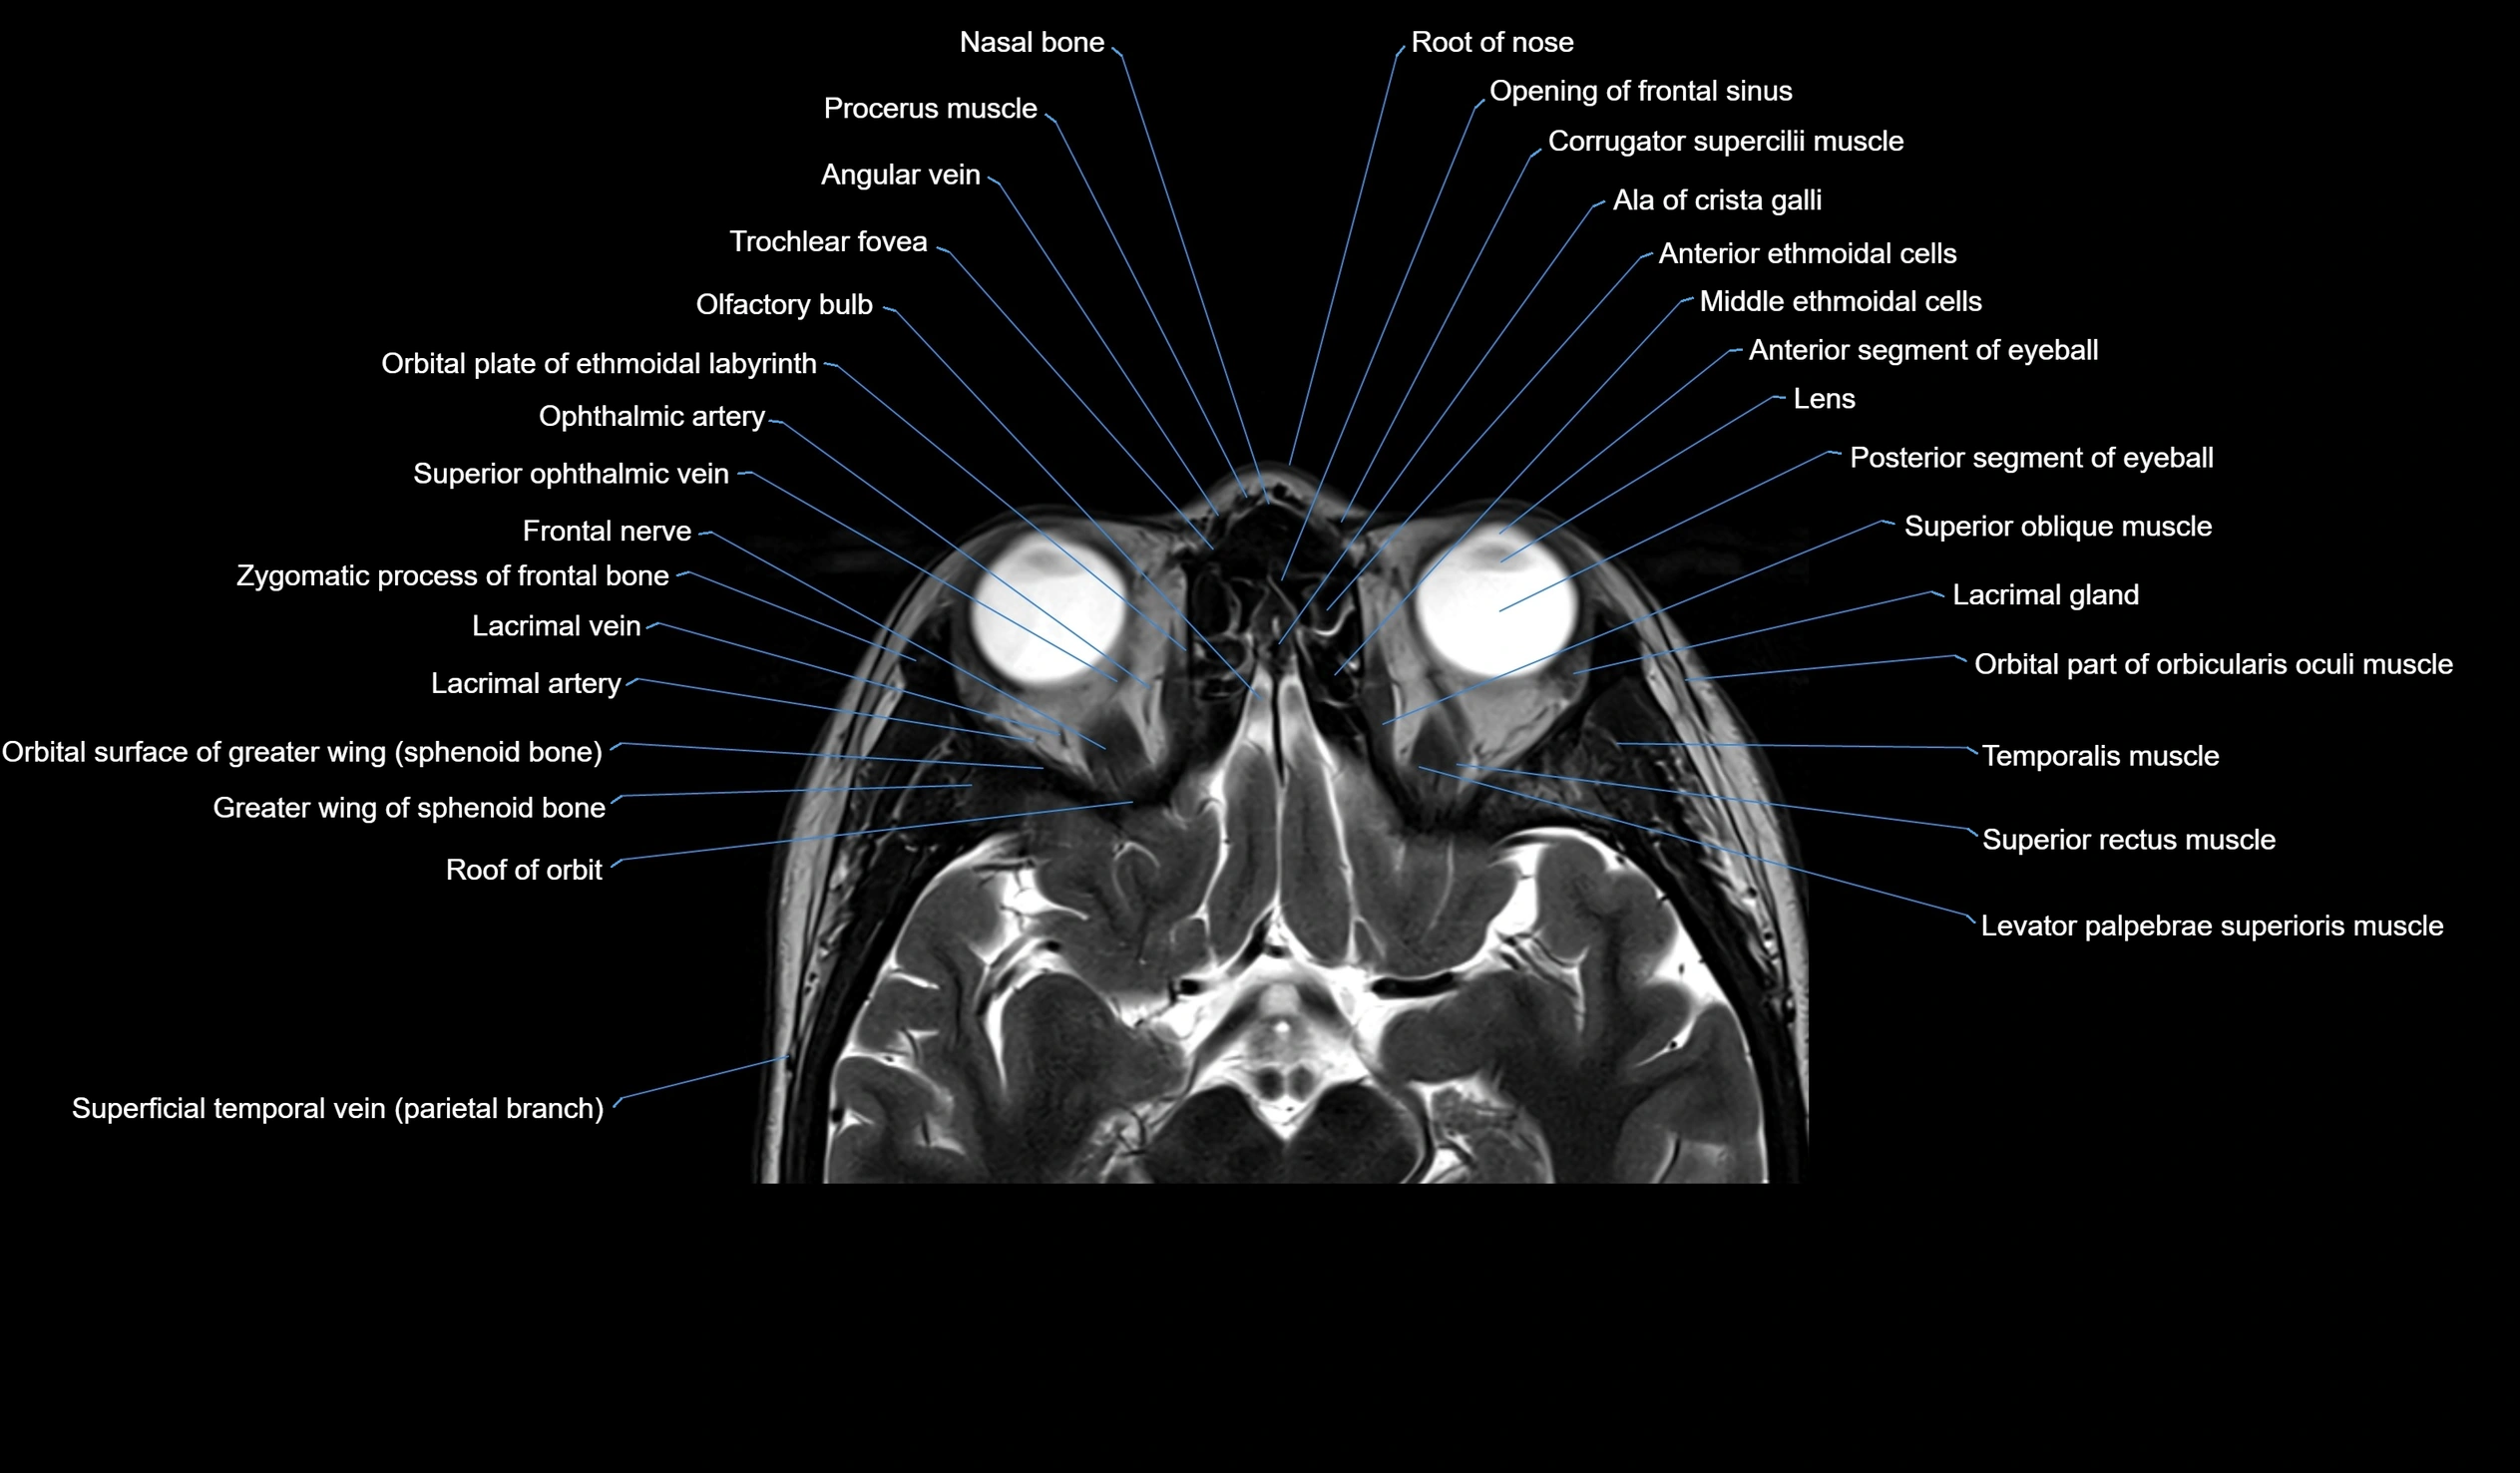

MRI images